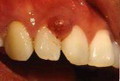

pregnancy gums enlargement

Hi po ,nabasa ko po dito yong about sa pregnancy gingivitis po. . Magtatanong din po sana ako ,sana po may makapansin na dentista or doctor na makapagbigay advice.. About po sa gums ko namamaga kasi nag start din po to noong second trimester ko .. Ano po dapat ko gawin,kasi wala dental clinic open dto sa amin and malayo po ang hospital sa amin..please po pa advice.. Ganyan na po sha sa pic mas malaki pa ...